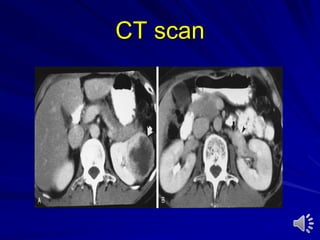

Computed tomography (CT) scan

With or without contrast medium

Indications:

– Stones

– Trauma

– Tumours

– Scaring of retroperitoneum

– Lymphadenopathy in genitourinary tumors

– Metastatic dissease

CT Scan